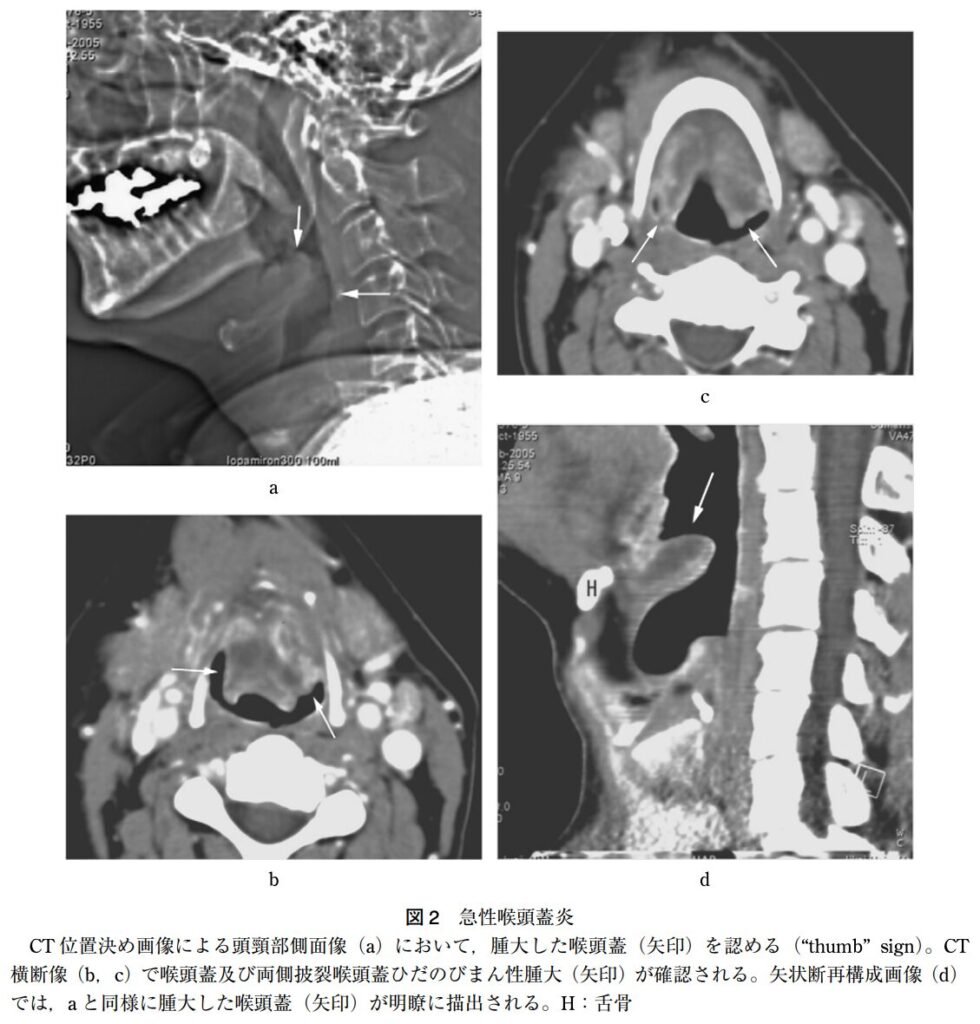

画像所見

頸部側面X線撮影

- 急性喉頭蓋炎を疑う際の頸部側面X線撮影における各所見の感度と特異度は以下の通りです。

- thumb sign(広く丸い喉頭蓋):感度 65.9~66.7%、特異度 94.0~100%

- vallecula sign(喉頭蓋谷の消失):感度 53.9~71.4%、特異度 88.1~100%

- 喉頭蓋幅>6.3 mm:感度 75.8%、特異度 97.8%

- これらのX線画像所見は、急性喉頭蓋炎の診断において基本となる喉頭ファイバー検査(喉頭蓋の腫脹や発赤の直接確認)の実施が困難な場合に有用とされています。

CT

- 仰臥位にすると腫大した喉頭蓋が気道を閉塞するおそれがあるため、CTは非常に危険であることを意識しないといけません。

- しかし、成人では小児に比べ気道が広いため必ずしも禁忌ではないといった文献もあります。⇢尾尻博也,耳展 53:6;441-442,2010